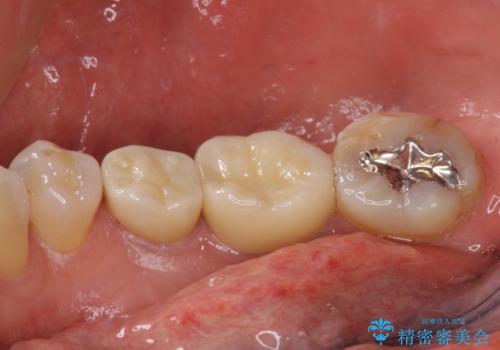

- セラミックが剥がれたり、歯質が欠けたりした奥歯を気にして来院された患者様です。

咬合力が強い方であったため、2歯をフルジルコニアクラウンにて補綴することとしました。